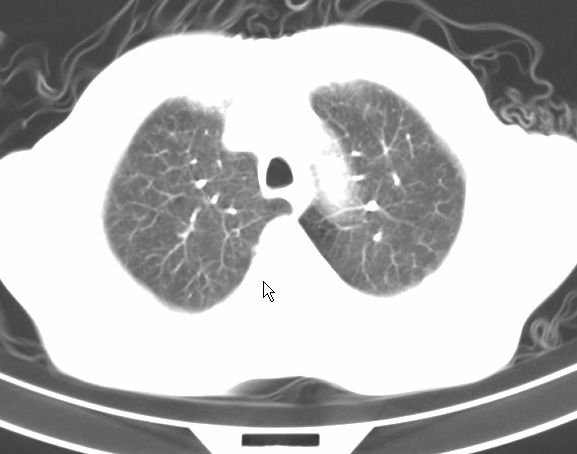

请大家看看是什么性质的。炎性病变首先考虑哪一种炎症。

支持右肺上叶前段\\下叶内基底段感染,建议抗炎治疗后复查,除外结核.

支持右肺上叶前段\\下叶上段感染,建议抗炎治疗后复查,除外结核.

支持右肺上叶前段、下叶内基底段感染,建议抗炎治疗后复查,除外结核.

右肺上叶前段及下叶内基底段感染性病变;建议抗炎治疗后复查。

楼主说是炎症,凭啥?典型的周围型肺癌(腺癌可能性大),肝内可能已有转移,强化看看吧。